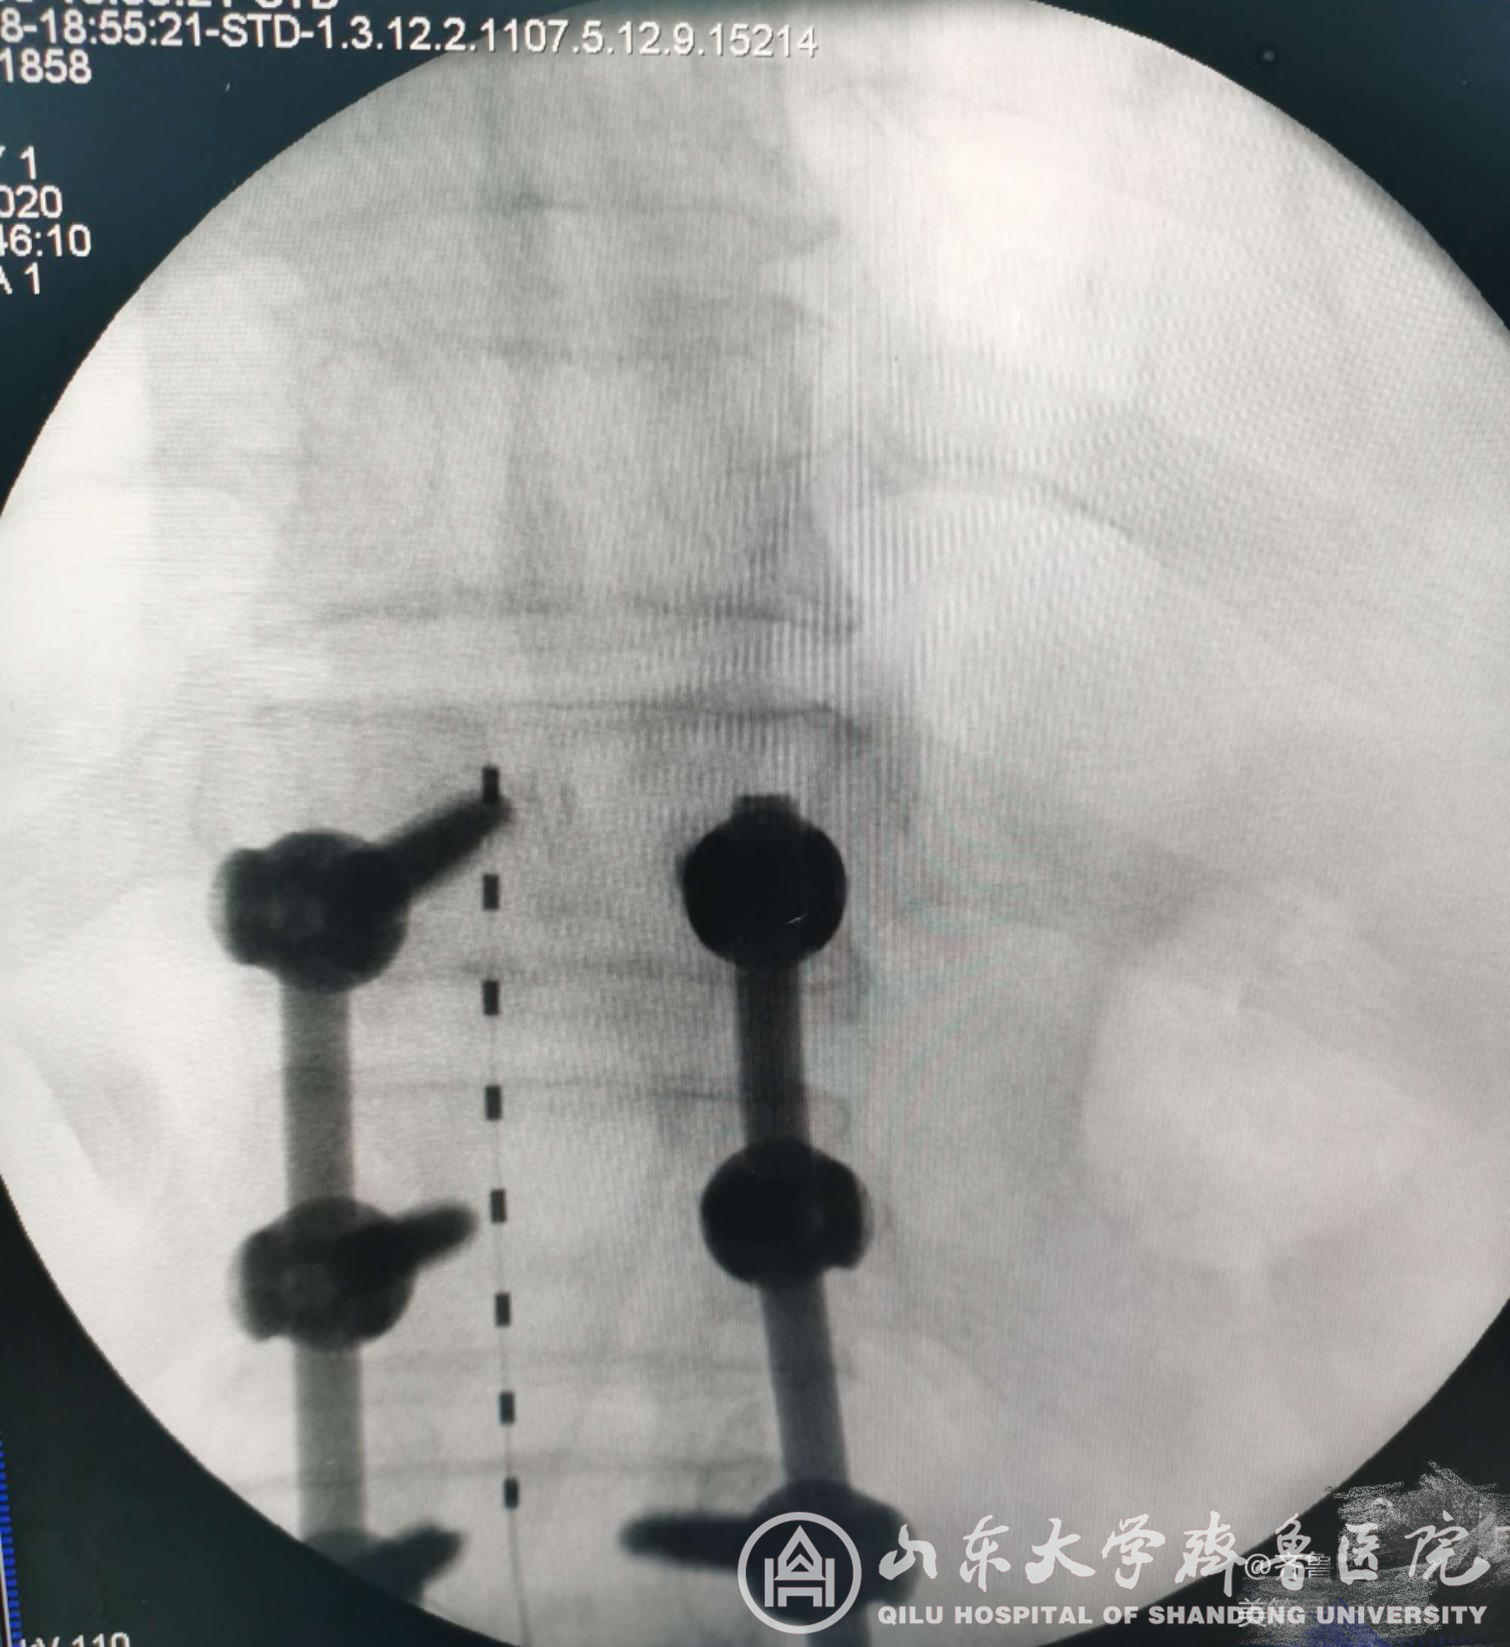

图3.电极测试良好